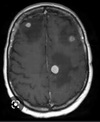

Metástases cerebrais Pontos hipertenso com edema perilesional